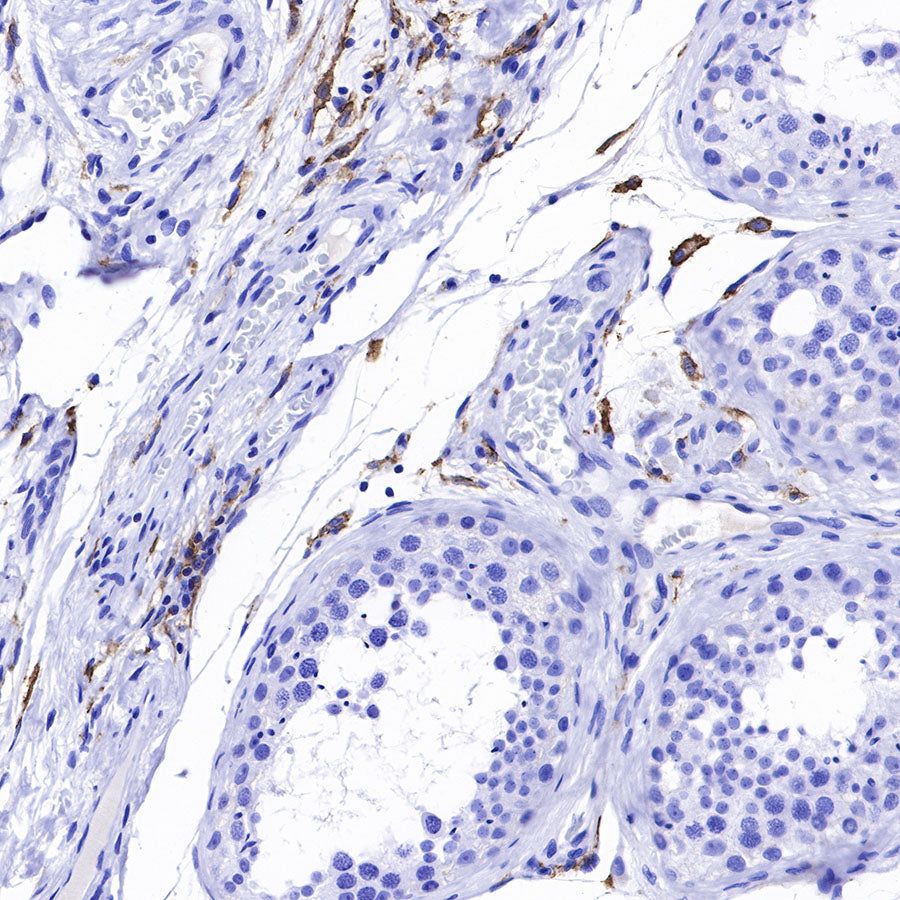

IHC shows positive staining in paraffin-embedded human testis. Anti-CD169 antibody was used at 1/250 dilution, followed by a HRP Polymer for Mouse & Rabbit IgG (ready to use). Counterstained with hematoxylin. Heat mediated antigen retrieval with Tris/EDTA buffer pH9.0 was performed before commencing with IHC staining protocol.